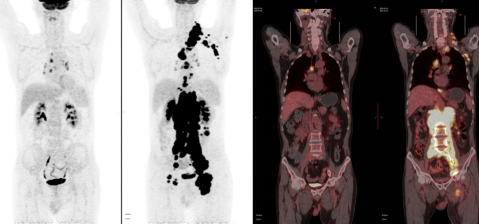

• 核医学科